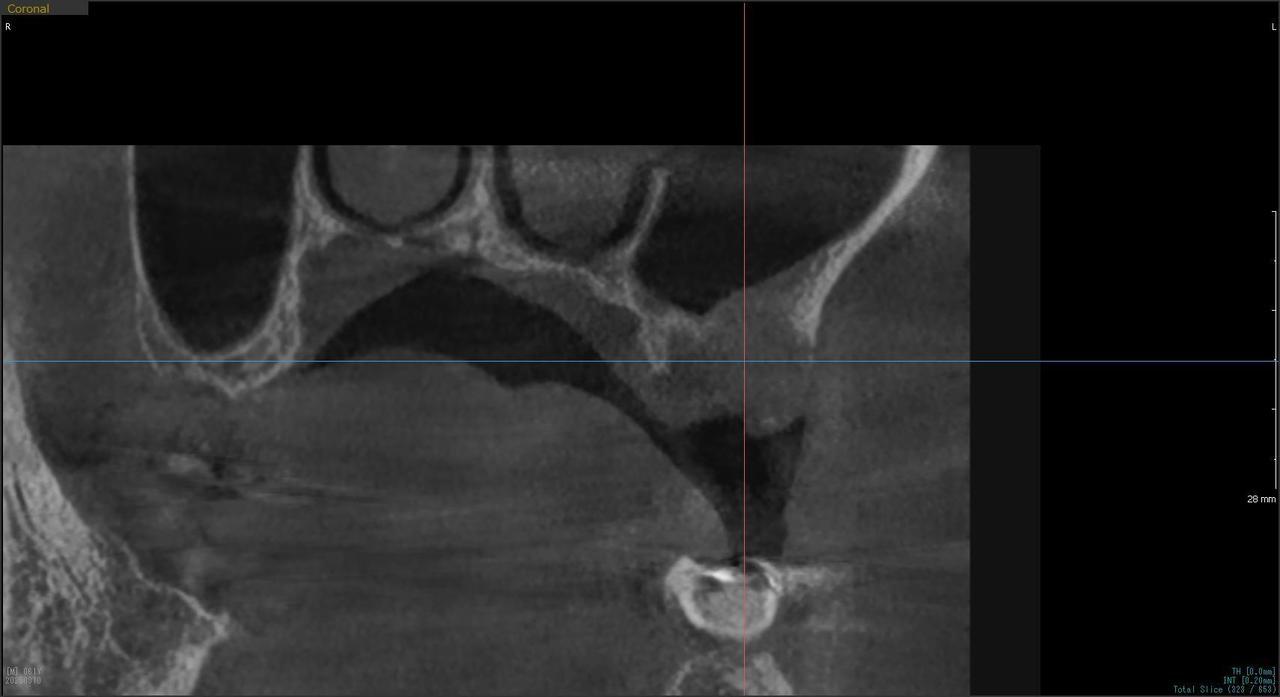

3.左上5の頬・舌側の大幅な骨欠損と上顎既存骨3mmまでの骨欠損がおこった症例に対しておこなったインプラント治療

I・K 様 女性 40代

症状としては、左上5の歯根破折を起こしていたため、排膿と自発痛をみとめた。それにともなう骨の大きな欠損。

治療法としては、炎症が強くたったためと、炎症による頬側側歯肉の退縮を認めていたために、まず、抜歯を行い上顎洞内及び歯抜した周囲組織の回復を試みた。その後、患者様がインプラント治療を希望したため、薄い上顎骨に対しては、グラフトレスサイナスリフト、骨欠損部には、人口骨補填を行い、頬側歯肉が退縮していることを改善するために、1回法でリーリングアバットメントを装着して、アバットメントの上に歯肉が覆うようにして、歯肉のボリューム回復を行った。2か月後、インプラントが骨と結合していることを確認して、光学印象を行い、2週間後にアバットメントとジルコニアクラウンを装着した。

治療結果としては、大幅な骨欠損があったが、グラフトレスサイナスリフトと骨欠損部に人工骨を補填して、抜歯した穴が自然に治る状態にしたことで、2か月半という短い期間での治療を完了することができた。(仮に、GBRや通常のサイナスリフトでの治療を行っていたら、最低でも1年は、かかってくる治療であると考える。)また、今回は、即時荷重を避け、1回法での治療を行ったことで、噛めない期間ができてしまったが、1回法で行ったことにより、歯肉のボリュームが増して、ブラッシングがしやすい口腔内環境にすることができた。低侵襲で、短時間で、治療を終えることができ、また、審美性・機能性の回復も行えたことができた。

治療の期間・回数:約2.5か月、6回

治療の価格:368,500円(税込)

治療費の内訳:インプラント基本料(フィックスチャー及び手術費用、投薬費用、レントゲン費用、インプラント上部費用(アバットメントおよびジルコニアクラウンの費用用)330000円(税込み)。オプション費用グラフトレスサイナスリフト費用プラス人工骨費用 38500円(税込み

治療のリスクや副作用:手術後に、痛みや腫れ、出血、合併症などを引き起こす可能性があります。噛む感覚がご自身の歯と異なる場合があります。見た目がご自身の歯と異なる場合があります。手術後にメインテナンスを継続しないと、インプラントが抜け落ちる可能性があります。